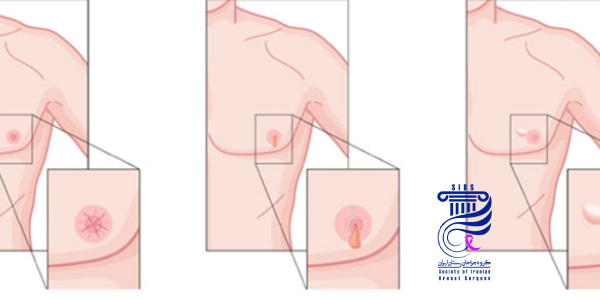

نمونهبرداری یا بیوپسی فرایندی است که در آن بافت مشکوک از پستان برداشته شده و برای بررسی دقیقتر به آزمایشگاه ارسال میشود. این بررسی پاتولوژیک کمک میکند تا نوع سرطان و ویژگیهای آن شناسایی شود. بیوپسی از طریق سوزن گذاری انجام میشود و نتیجه آن به تعیین مرحله بیماری و انتخاب روش درمانی مناسب کمک میکند.

در صورت نیاز، بازسازی سینه

در صورت نیاز، جراحی بازسازی سینه، هم زمان با جراحی برداشت سینه یا در مراحل بعدی انجام میشود. این بازسازی با استفاده از پروتز یا بافت بدن انجام میگیرد و هدف آن بازگرداندن ظاهر طبیعی سینه و بهبود روحیه بیمار بعد از عمل است. انتخاب روش بازسازی به شرایط بدنی و ترجیح بیمار بستگی دارد.

بازسازی سینه چه زمانی انجام میشود؟

بازسازی سینه میتواند همزمان با جراحی برداشت سینه یا مدتی بعد از آن انجام شود. این موضوع به شرایط جسمی بیمار، برنامه درمانی و ترجیح شخصی بستگی دارد.